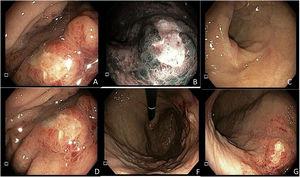

A 59-year-old man, with an unremarkable past medical history, came to the emergency department on two occasions due to epigastric pain, melena, diaphoresis, and dyspnea, of seven-day progression. The initial evaluation showed anemia (hemoglobin: 9.7 g/dl) and hemodynamic stability, for which he received outpatient management with oral omeprazole. He sought medical attention 48 h later because of hematochezia. Upper gastrointestinal endoscopy identified a 10 × 10 mm lesion with a neoplastic aspect in the gastric body, toward the greater curvature, with surrounding infiltrate-like mucosa (Fig. 1). Numerous biopsy samples were taken that contained deposits of pale pink interstitial and extracellular material with a thick and cracked hyaline appearance. Congo Red staining produced a salmon-pink color that, under polarized light, showed apple-green birefringence (Fig. 2).

Upper gastrointestinal endoscopy, showing a 10 mm × 10 mm lesion with a neoplastic appearance in the gastric body toward the greater curvature. (1A) Elevated lesion in the greater curvature, with a depressed center and irregular edges, Paris 0-IIa + 0-Iic, under direct light. (1B) Lesion with a trabecular surface, with branched and irregular areas, of heterogeneous color and a vascular pattern with areas presenting with amputated vessels under narrow band imaging (NBI), in the greater curvature of the gastric body. (1C) Gastric antrum with no apparent endoscopic lesions. (1D) Lesion viewed from the lesser curvature, with no magnification. (1F) Gastric retroflexion in which the lesion and gastric fundus with normal mucosa can be seen. (1G) Direct view of the entire gastric body.